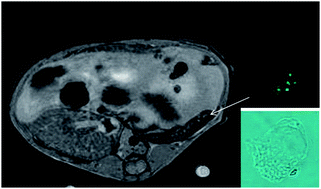

This study aims to investigate gadolinium-based nanoparticles (Gd-HNP) for in vitro labeling of human plasmacytoid dendritic cells (HuPDC) to allow for in vivo tracking and HuPDC quantifying using magnetic resonance imaging (MRI) following parenteral injection. Human plasmacytoid DC were labeled (LabHuPDC) with fluorescent Gd-HNP (Gd-FITC-HNP) and injected via intraperitoneal and intravenous routes in 4–5 NOD-SCID β2m-/-mice (treated mice = TM). Control mice (CM) were similarly injected with unlabeled HuPDC. In vivo 7 T MRI was performed 24 h later and all spleens were removed in order to measure Gd and fluorescence contents and identify HuPDC. Gd-FITC-HNP efficiently labeled HuPDC (0.05 to 0.1 pg per cell), without altering viability and activation properties. The magnetic resonance (MR) signal was exclusively due to HuPDC. The normalized MR splenic intensity for TM was significantly higher than for CM (p < 0.024), and highly correlated with the spleen Gd content (r = 0.97), and the number of HuPDC found in the spleen (r = 0.94). Gd-FITC-HNP allowed for in vivo tracking and HuPDC quantifying by means of MRI following parenteral injection, with very high sensitivity (<3000 cells per mm3). The safety of these new nanoparticle types must be confirmed via extensive toxicology tests including in vivo stability and biodistribution studies.